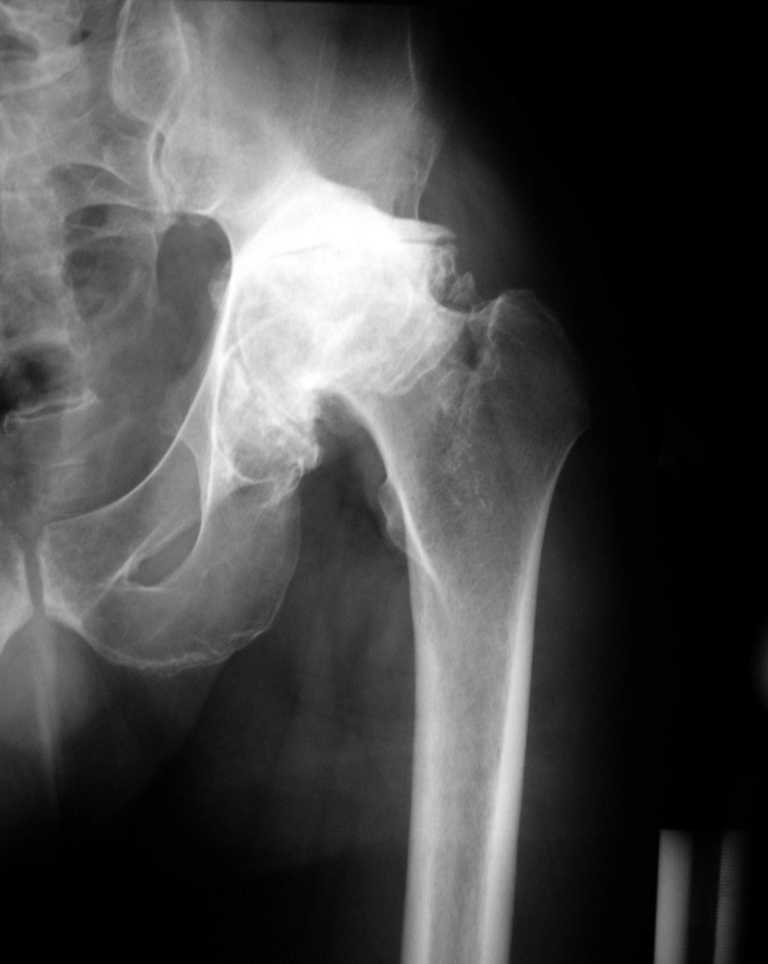

Еще одно наблюдение, неправильно сросшийся перелом заднего отдела ВВ с ввихом головки бедра 16-и летней давности.

С уважением, Р.Тихилов